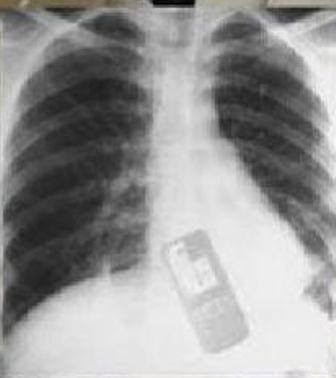

Gilanya, dari hasil rontgen diketahui kalau saiz telefon tersebut cukup besar. Tidak disebutkan pula, telefon bimbit apa yang ditelan Adriana. Untuk mengeluarkan telefon tersebut, pihak rumah sakit melakukan prosedur pembedahan untuk mengeluarkannya